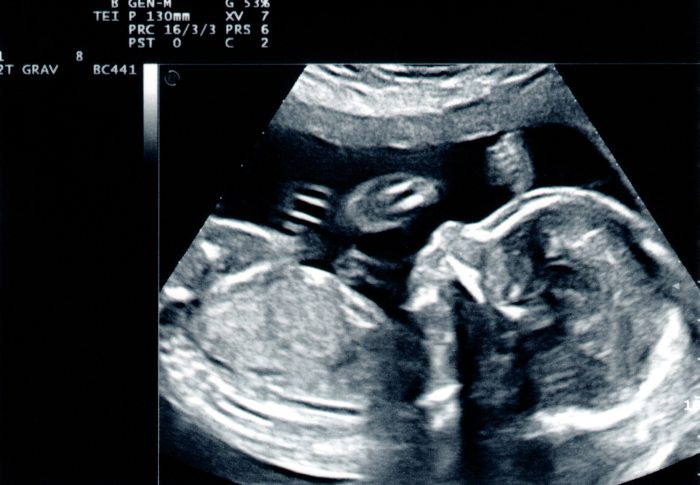

W toku dążenia do rozpoznania, lekarze mogą zaproponować szereg badań – od ultrasonografii przez laparoskopię, jak również badania rezonansem magnetycznym, które pozwolą ujrzeć to, co zazwyczaj skryte jest przed ludzkimi oczami. Każda z tych metod może wnieść inwazję w codzienne życie pacjentki, co w konsekwencji rodzi skrywany niepokój i obawę przed nieznanym. Niemniej jednak, rozwianie wątpliwości, a tym samym kierunek leczenia, są o wiele ważniejsze niż chwilowy dyskomfort.